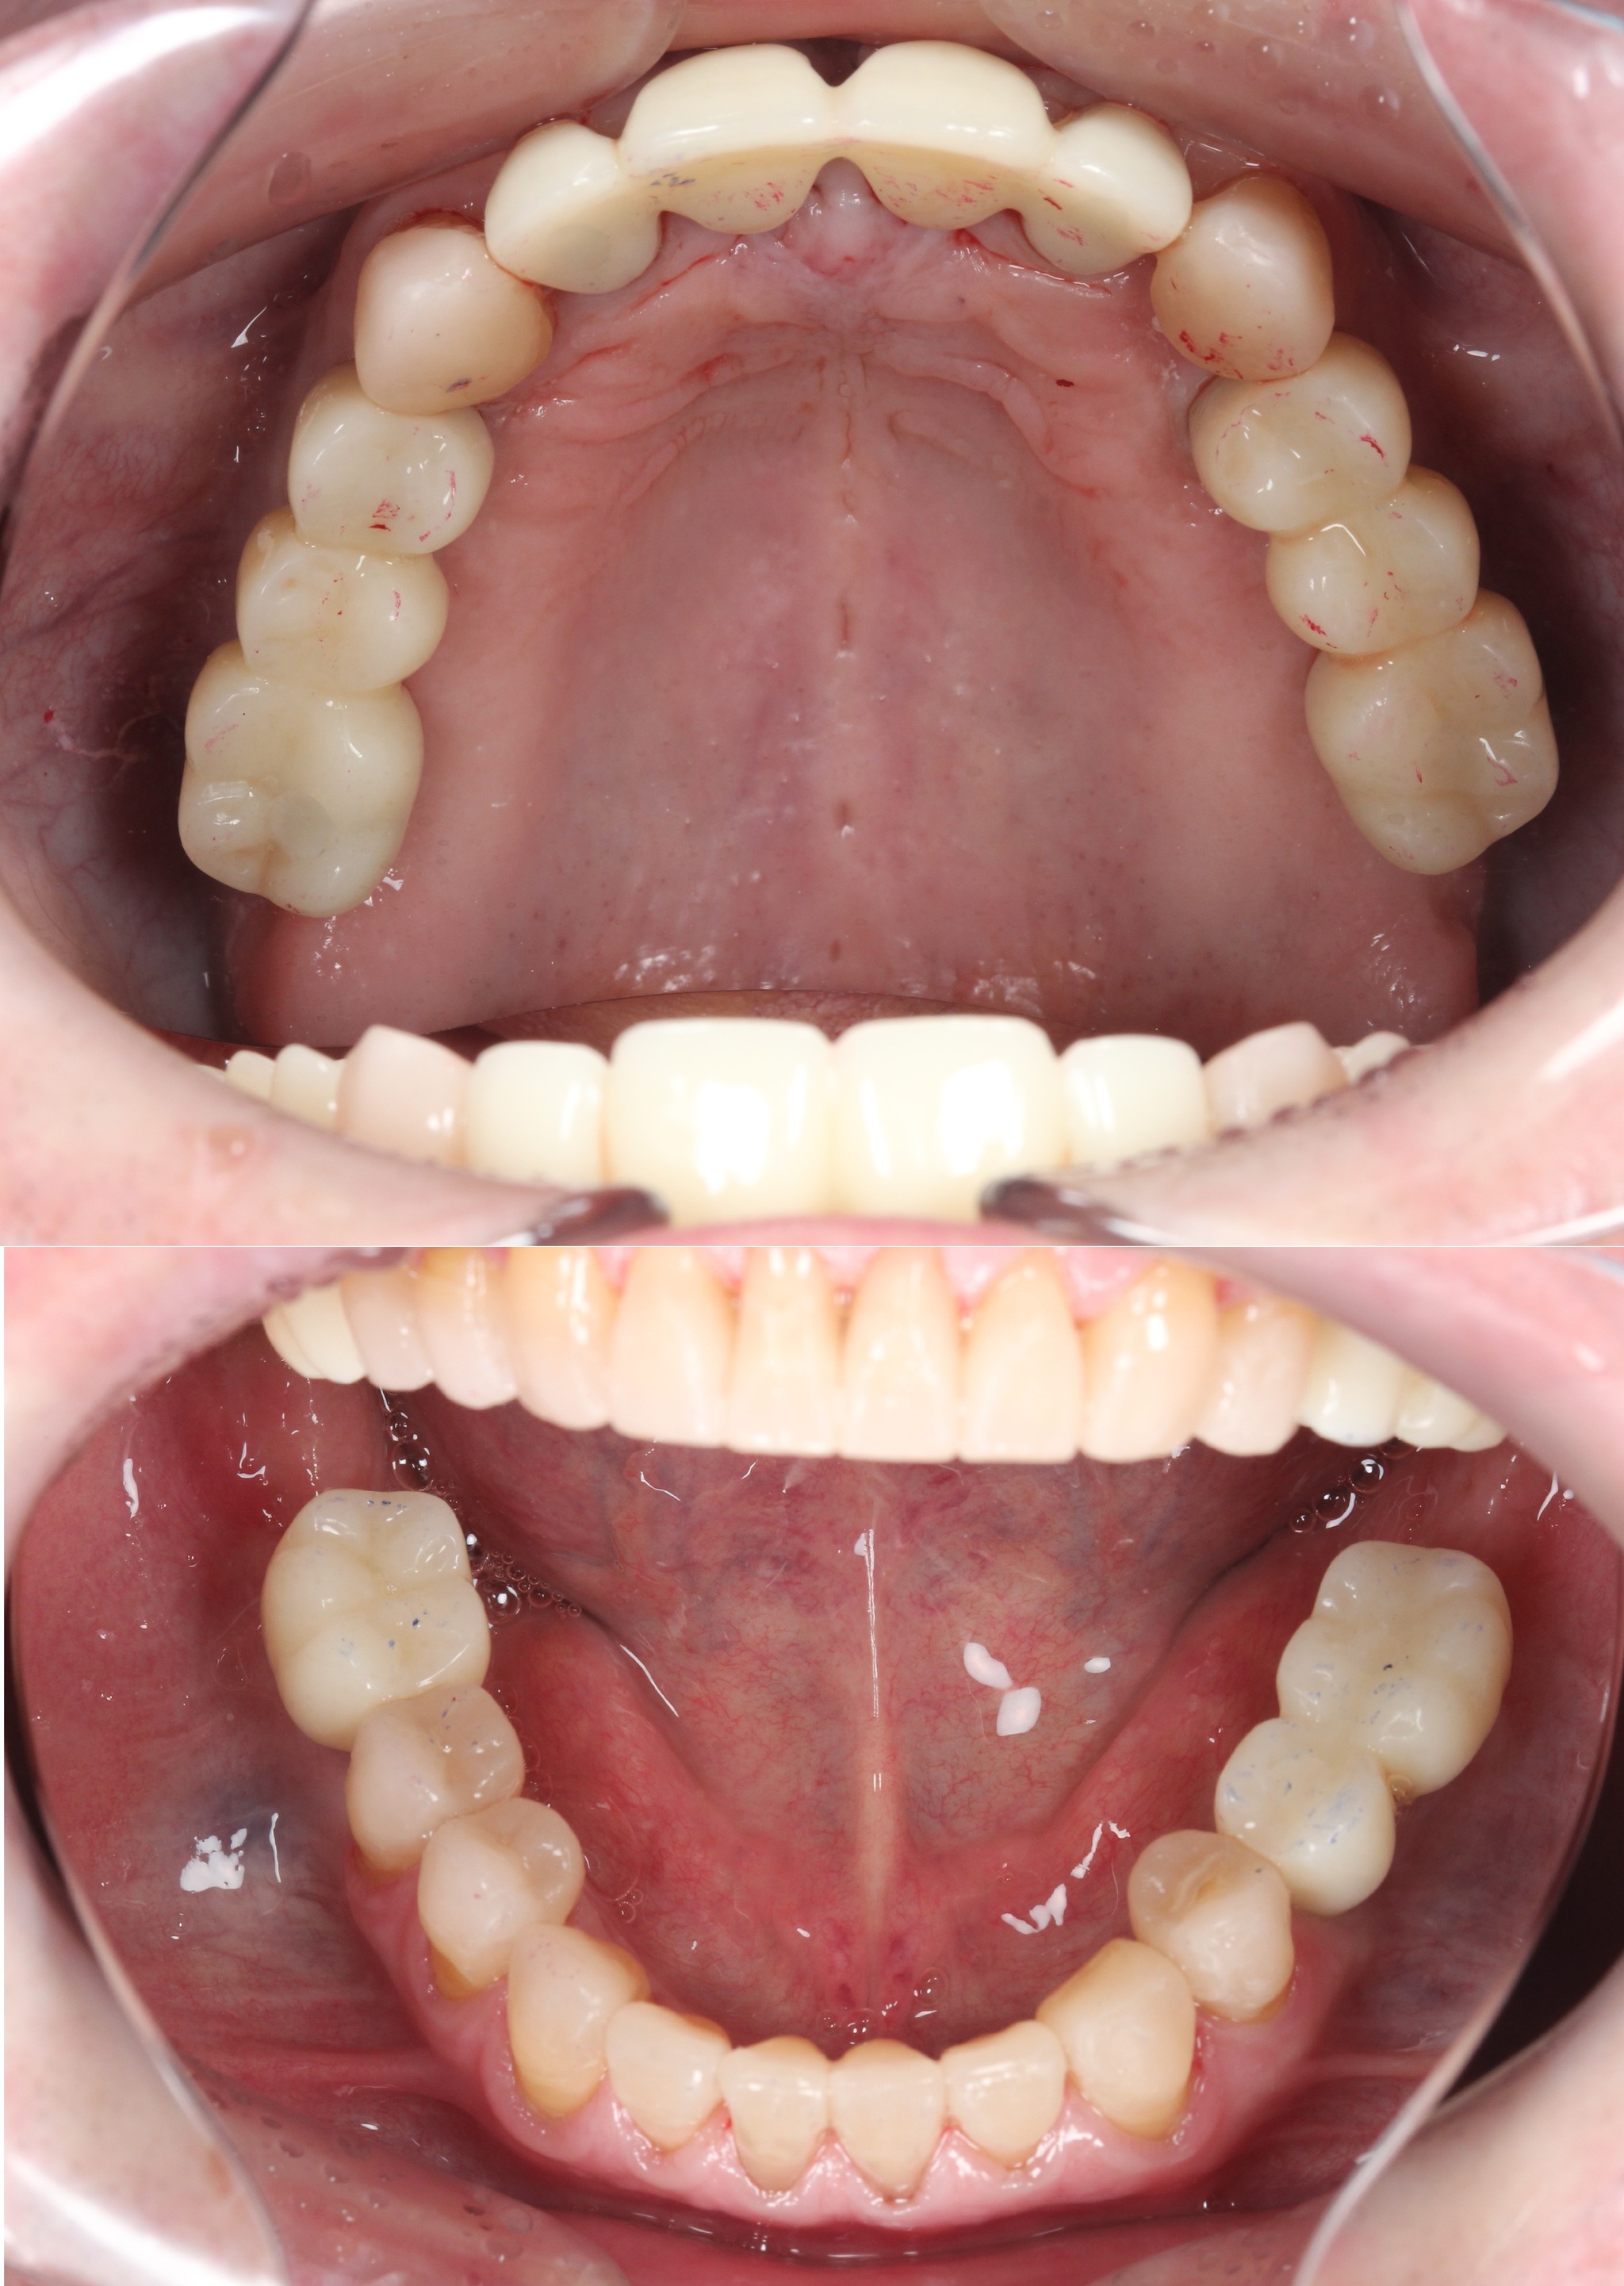

После чего пациент был направлен к ортопеду на слепки:

Спустя две недели произведена фиксация временных коронок.

Коронки на имплантатах на нижней челюсти:

Подчеркну - коронки временные (!), все они будут заменены на постоянные.